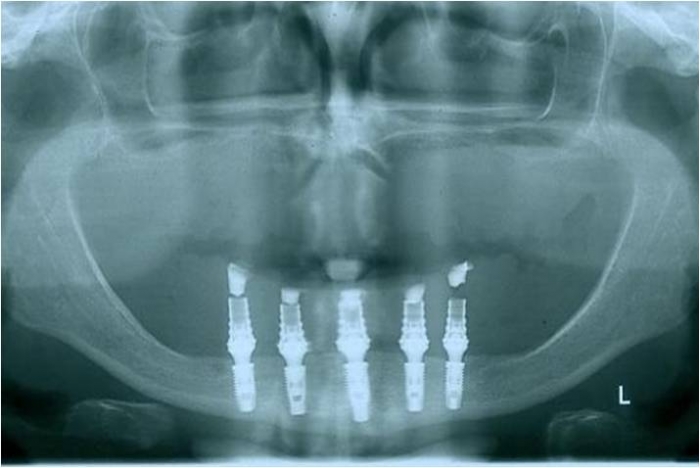

Raio x após prótese imediata fixa inferior e nova prótese superior, provisórias instaladas - Clínica Cliniface

Raio x após prótese imediata fixa inferior e nova prótese superior, provisórias instaladas